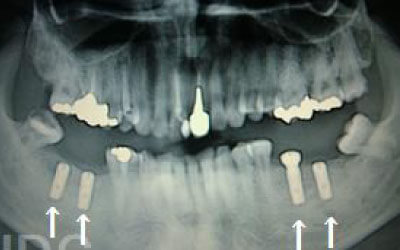

CTでは、骨や歯の状態を三次元で確認でき、正確な距離を測定することができます。

骨の厚さや傾き、神経の位置などを事前に詳しく計測することで、安全にインプラントを行うことができます。

しかし、事前にCTでしっかりと撮影し、三次元的に神経との距離を計測して治療計画を立てることで、心配は不要です。

また、当院では削りすぎを防ぐためのストッパーも使用しています。